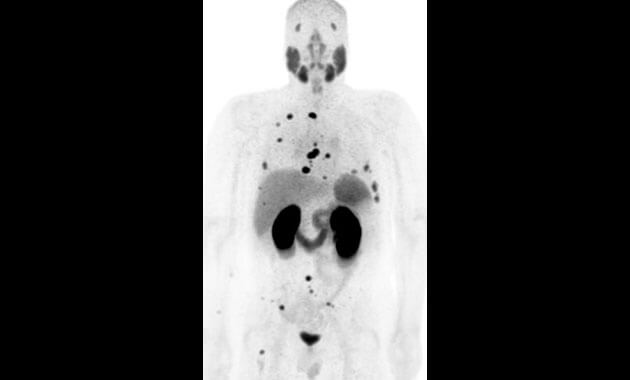

- Cancer

- Infection

- Neurodegenerative disease